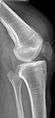

Quadriceps tendon rupture in plain X-ray